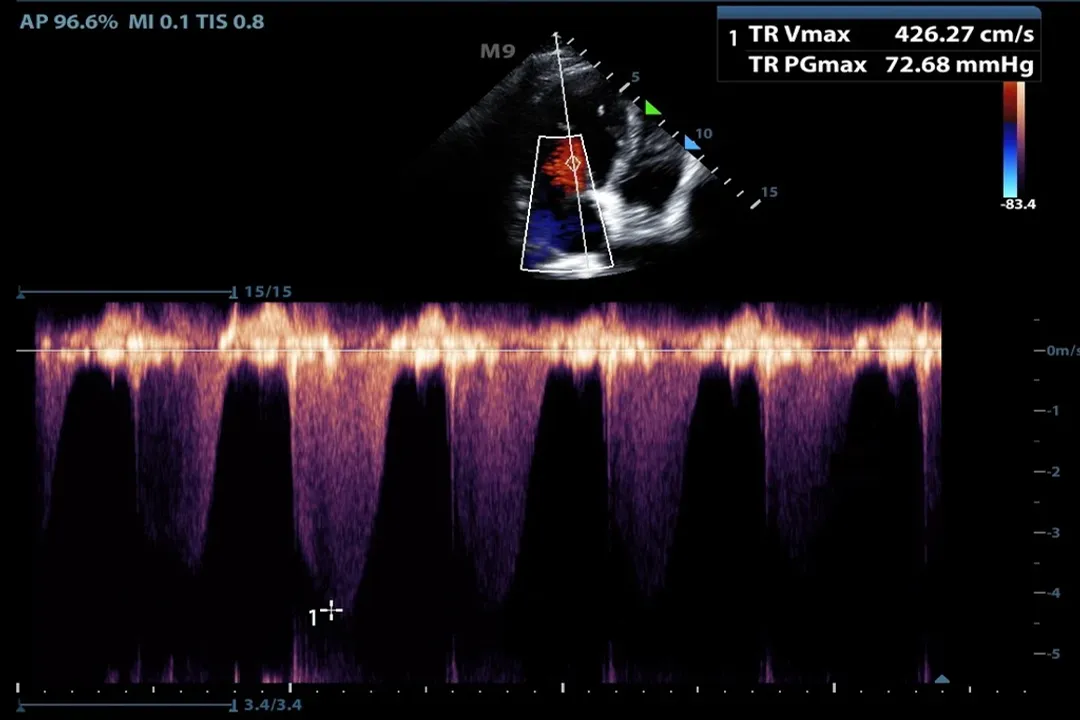

While B-mode shows anatomy, Doppler ultrasound reveals movement within the anatomy, most importantly blood flow. [4][6] This relies on the Doppler effect—the change in frequency of a wave in relation to an observer who is moving relative to the wave source. [8]

When the sound beam reflects off moving red blood cells, the frequency of the returning echo is slightly higher or lower than the frequency that was sent out, depending on the direction of flow relative to the probe. [5][6]

Doppler is typically displayed in a few ways:

• Color Doppler: Overlays color onto the B-mode image. Red might represent flow moving toward the transducer, while blue represents flow moving away, giving an immediate visual map of circulation paths. [6]

• Pulsed Wave or Continuous Wave Doppler: Provides a spectral display (a graph) of the velocity and direction of flow over time, which is crucial for assessing the severity of blockages or leaks in vessels or heart valves. [5][6]